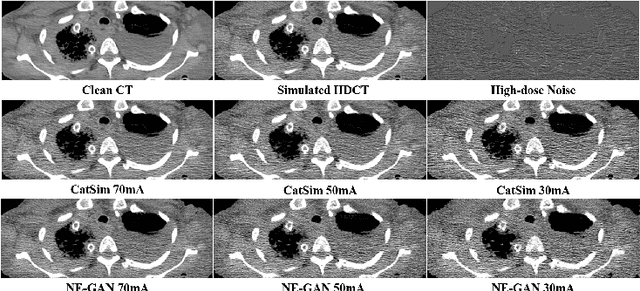

Abstract:We propose a Noise Entangled GAN (NE-GAN) for simulating low-dose computed tomography (CT) images from a higher dose CT image. First, we present two schemes to generate a clean CT image and a noise image from the high-dose CT image. Then, given these generated images, an NE-GAN is proposed to simulate different levels of low-dose CT images, where the level of generated noise can be continuously controlled by a noise factor. NE-GAN consists of a generator and a set of discriminators, and the number of discriminators is determined by the number of noise levels during training. Compared with the traditional methods based on the projection data that are usually unavailable in real applications, NE-GAN can directly learn from the real and/or simulated CT images and may create low-dose CT images quickly without the need of raw data or other proprietary CT scanner information. The experimental results show that the proposed method has the potential to simulate realistic low-dose CT images.